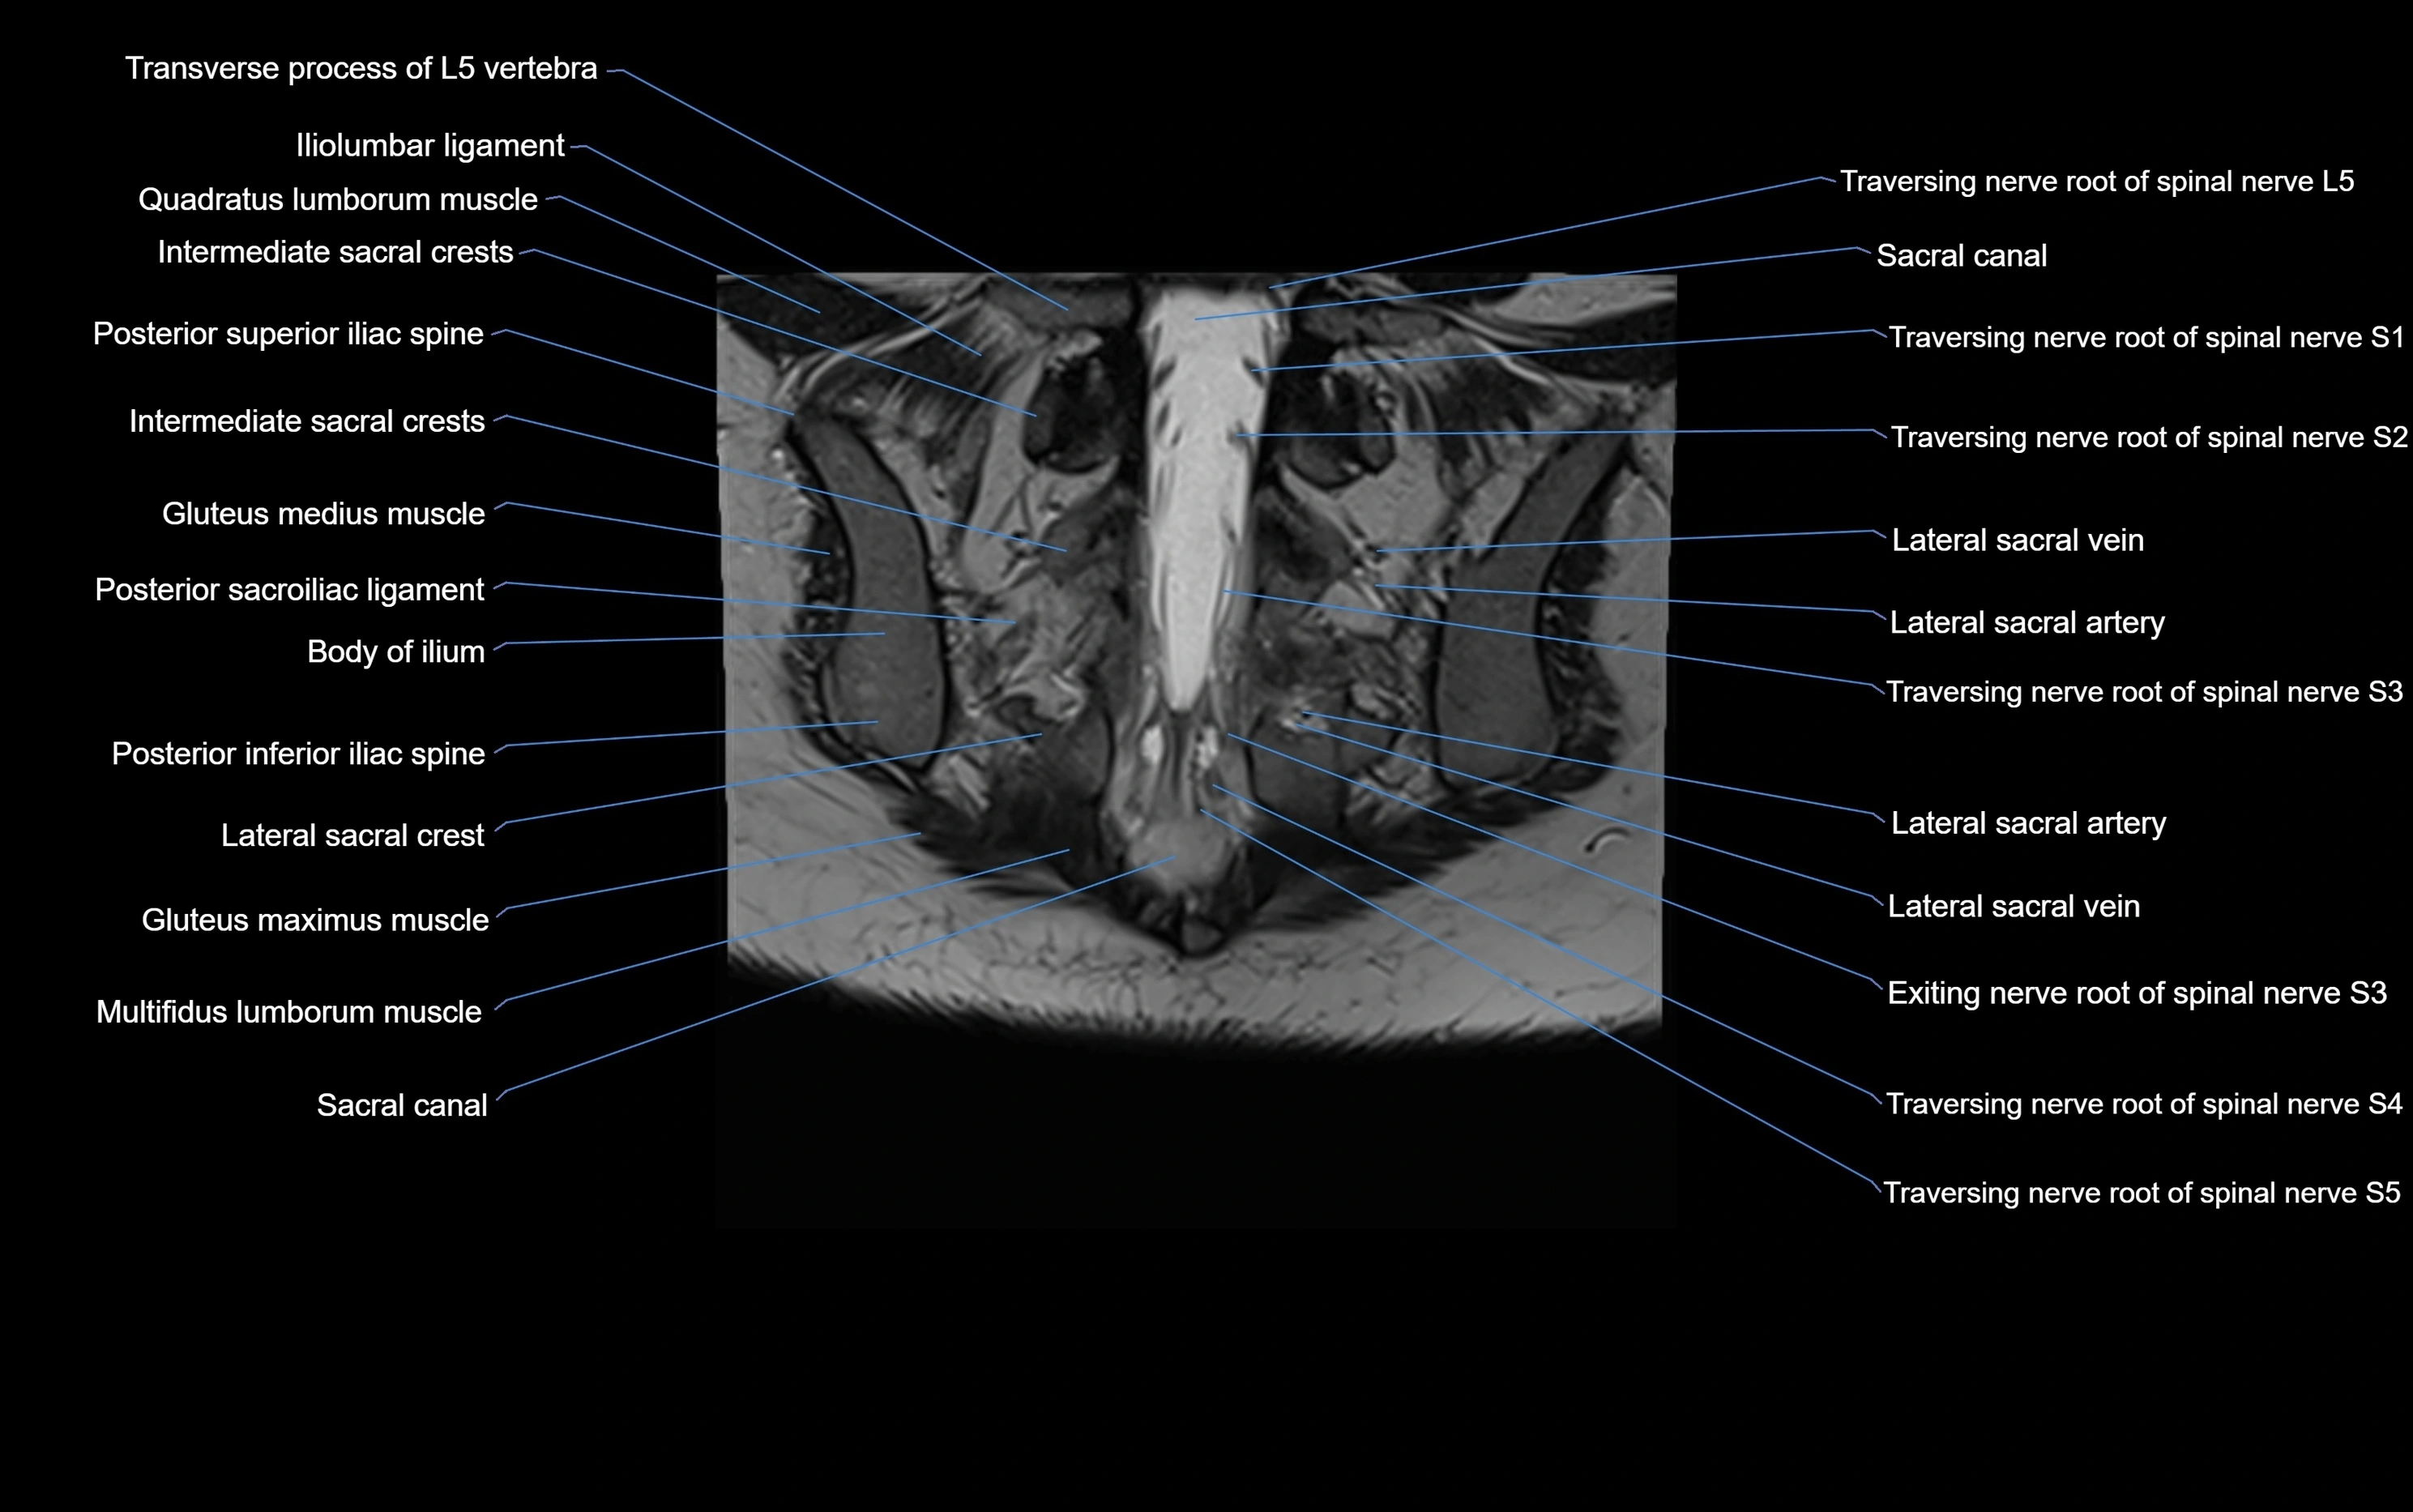

CT VRT image

image